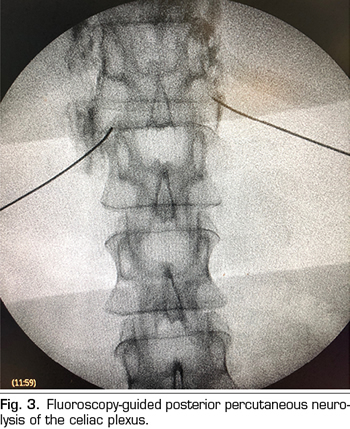

Transcrural approach: the most commonly used for the blockage of the celiac plexus (Figure 3). The patient is placed in prone position, identifying the vertebral body L1 and advancing a needle on each side, approximately 7.5 cm from the midline, until it crosses the diaphragmatic crura and blocks the plexus.

Percutaneous celiac plexus neurolysis consists in the destruction of the fibers composing the celiac plexus by injecting a neurolytic agent, the use of alcohol is preferred due to its lower affinity for blood vessels compared to phenol. The most commonly used classical approach is the bilateral transcrural posterior, guided by fluoroscopy or CT.